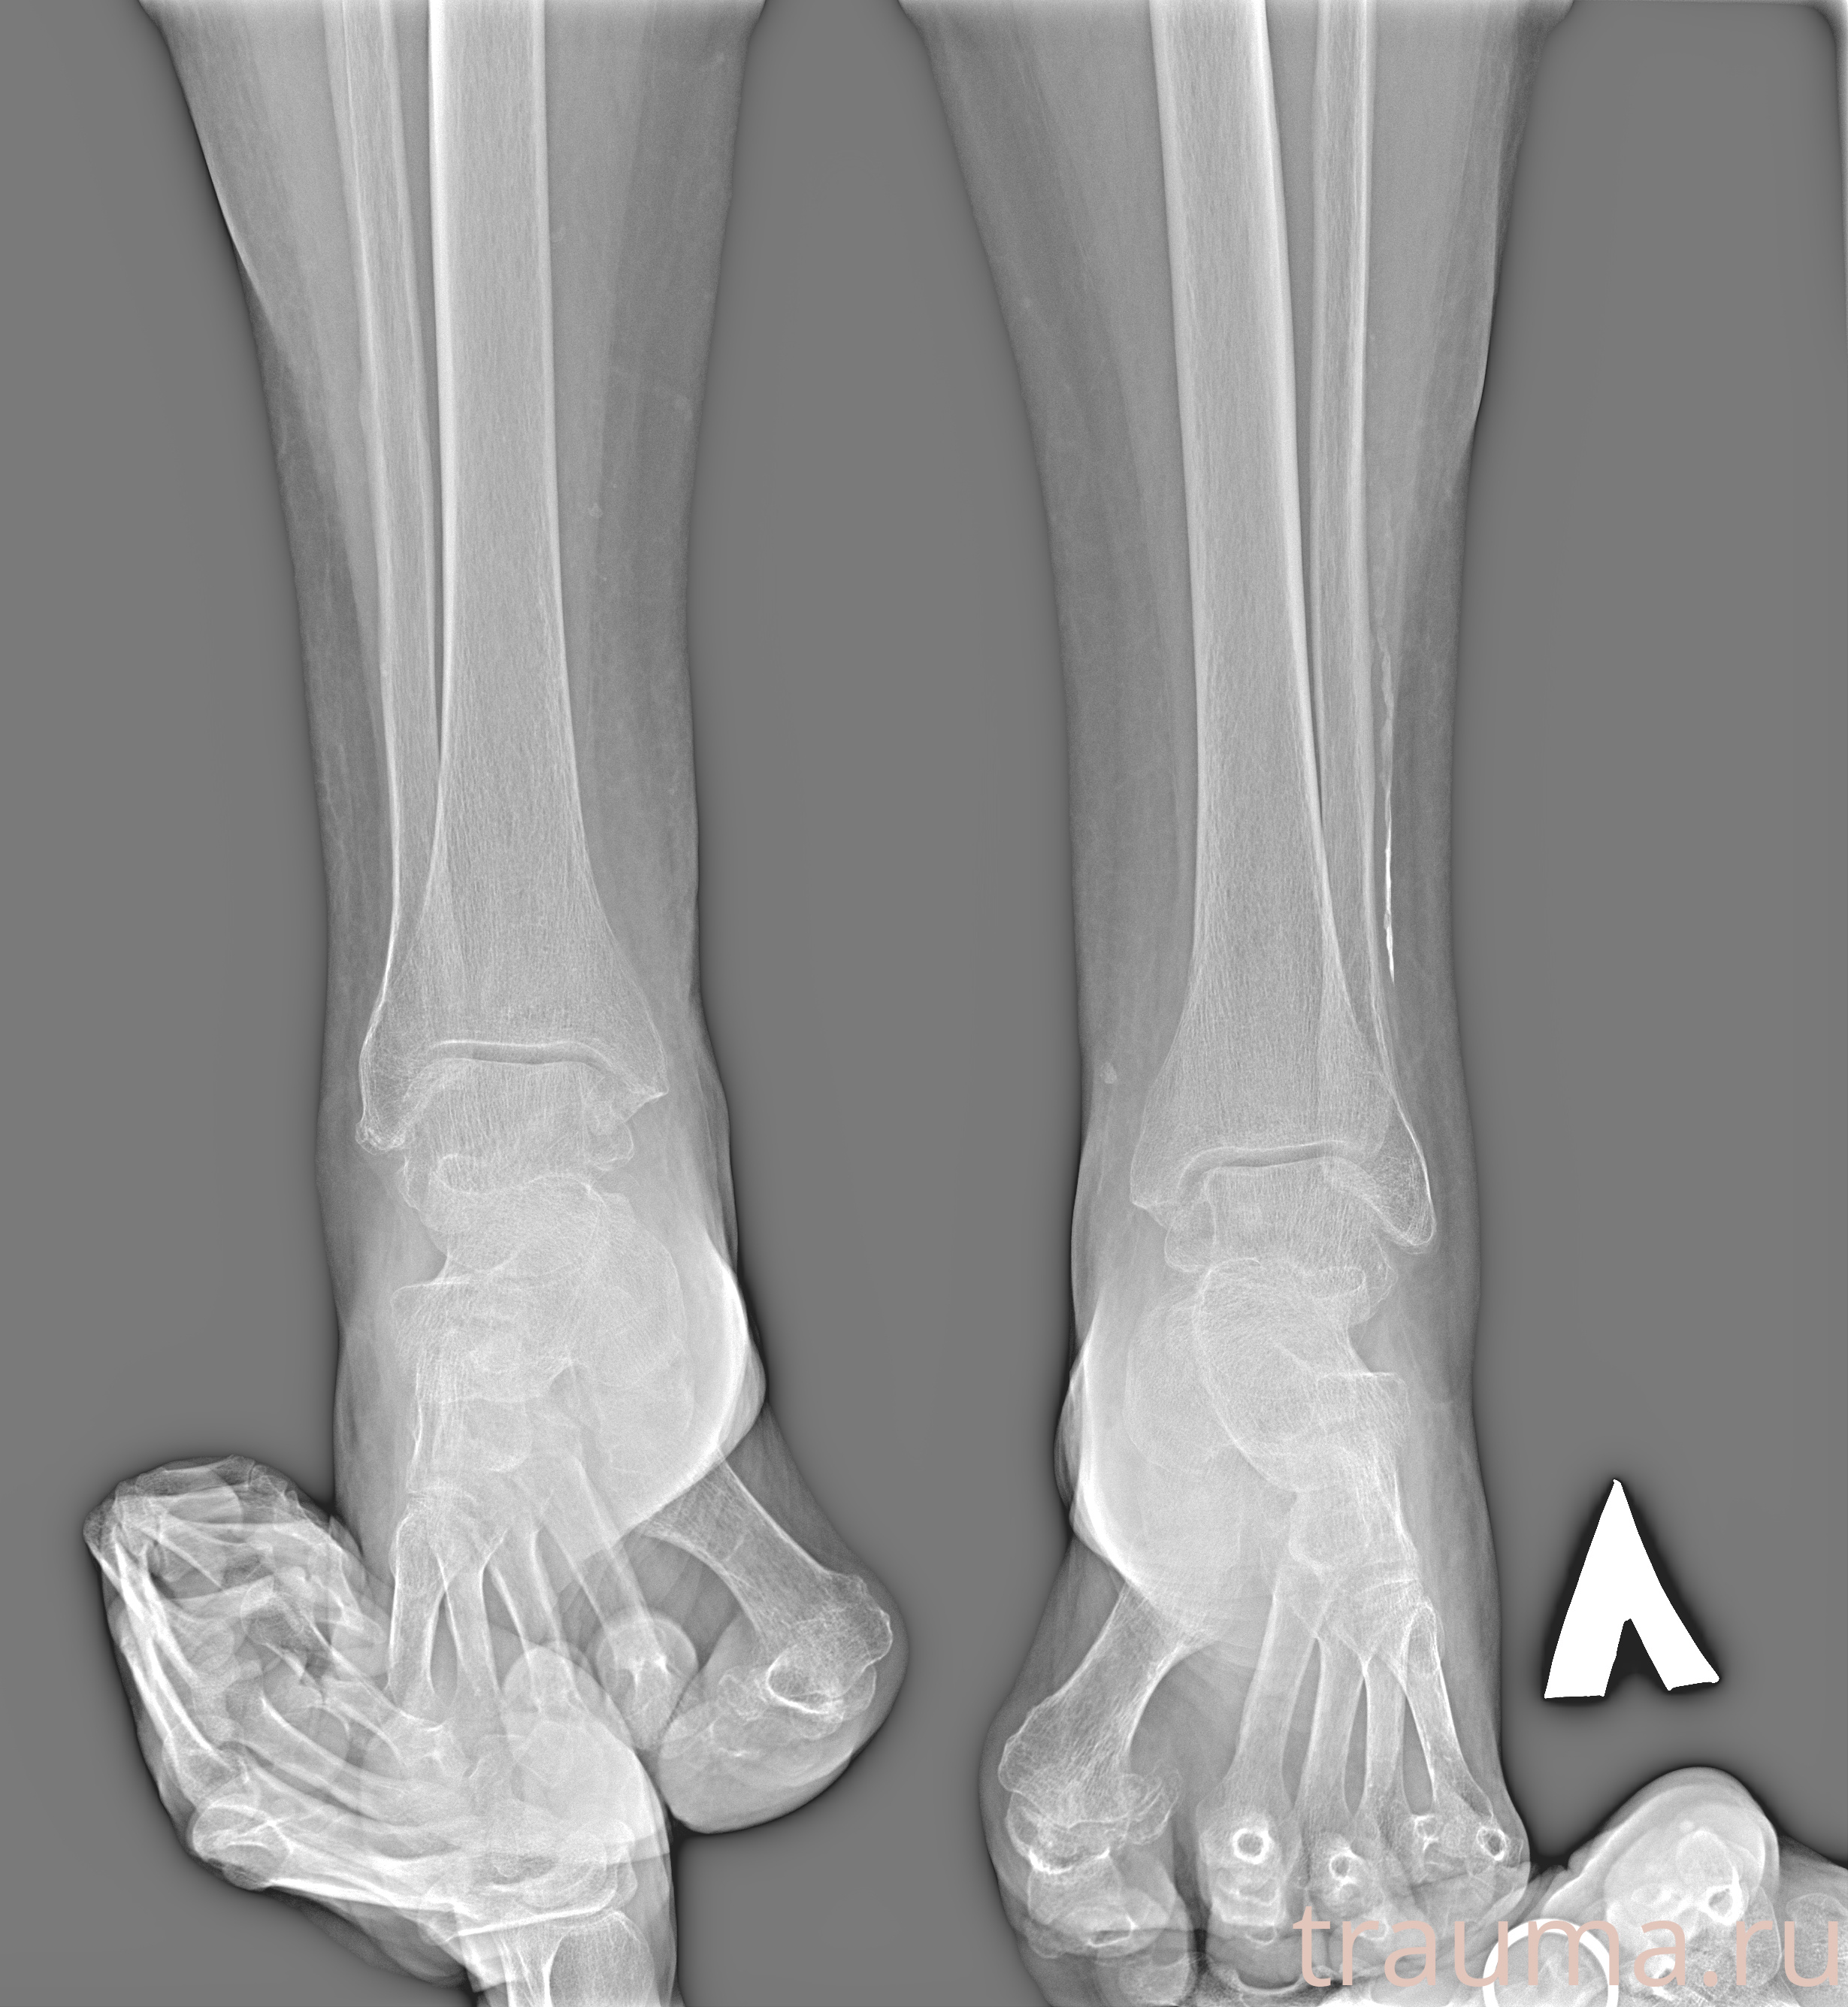

Рентген на дому: по вашему адресу приезжает врач-рентгенолог, травматолог-ортопед с мобильным рентгеновским аппаратом, проводит диагностику травмы или заболевания, делает необходимые рентгенограммы, дает рекомендации по дальнейшему лечению. Получить качественные снимки в домашних условиях возможно благодаря уникальной методике, разработанной МосРентген Центром для института  Склифосовского